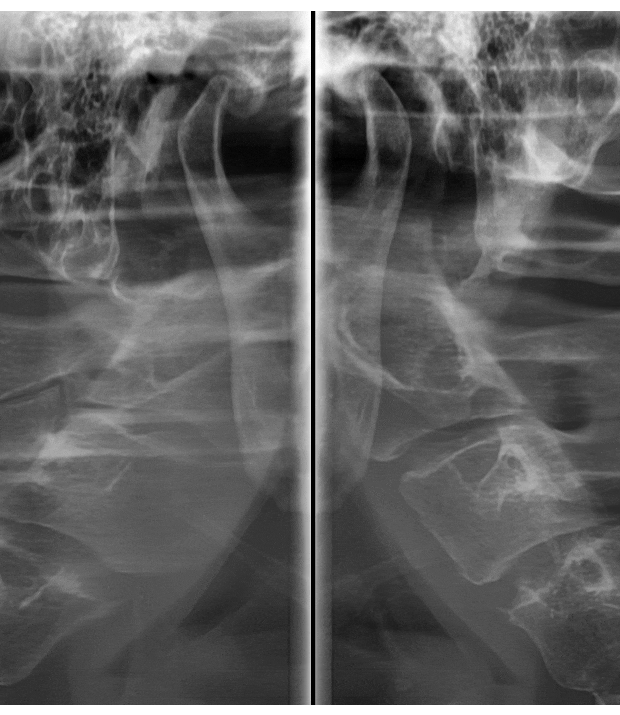

턱관절만 확인할 수 있는 x-ray 촬영도 가능합니다!